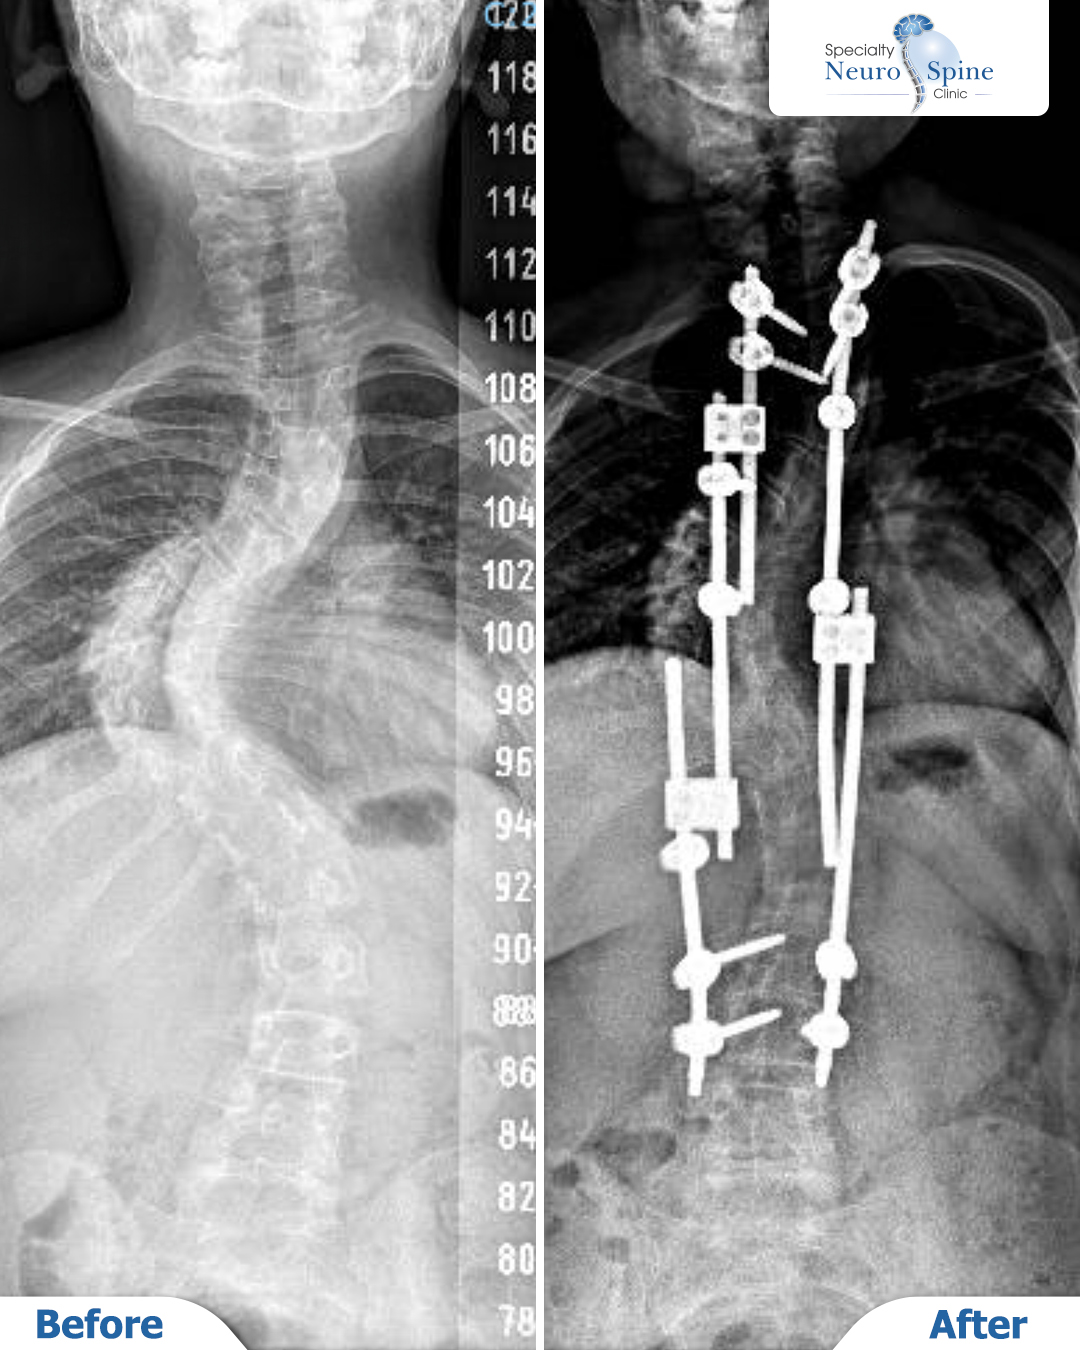

X-ray images of our young hero, Saba from Syria, now 14 years old, following her spinal curvature correction surgery performed in 2021 when she was ten.

The procedure covered the vertebrae from the 2nd thoracic vertebra (T2) to the 3rd lumbar vertebra (L3). It was performed using the Vertebral Body Tethering (VBT) technique—a growth-modulation method designed to correct curvature while preserving the spine’s natural growth.

The images demonstrate significant improvement in spinal alignment and continued, balanced growth post-surgery.